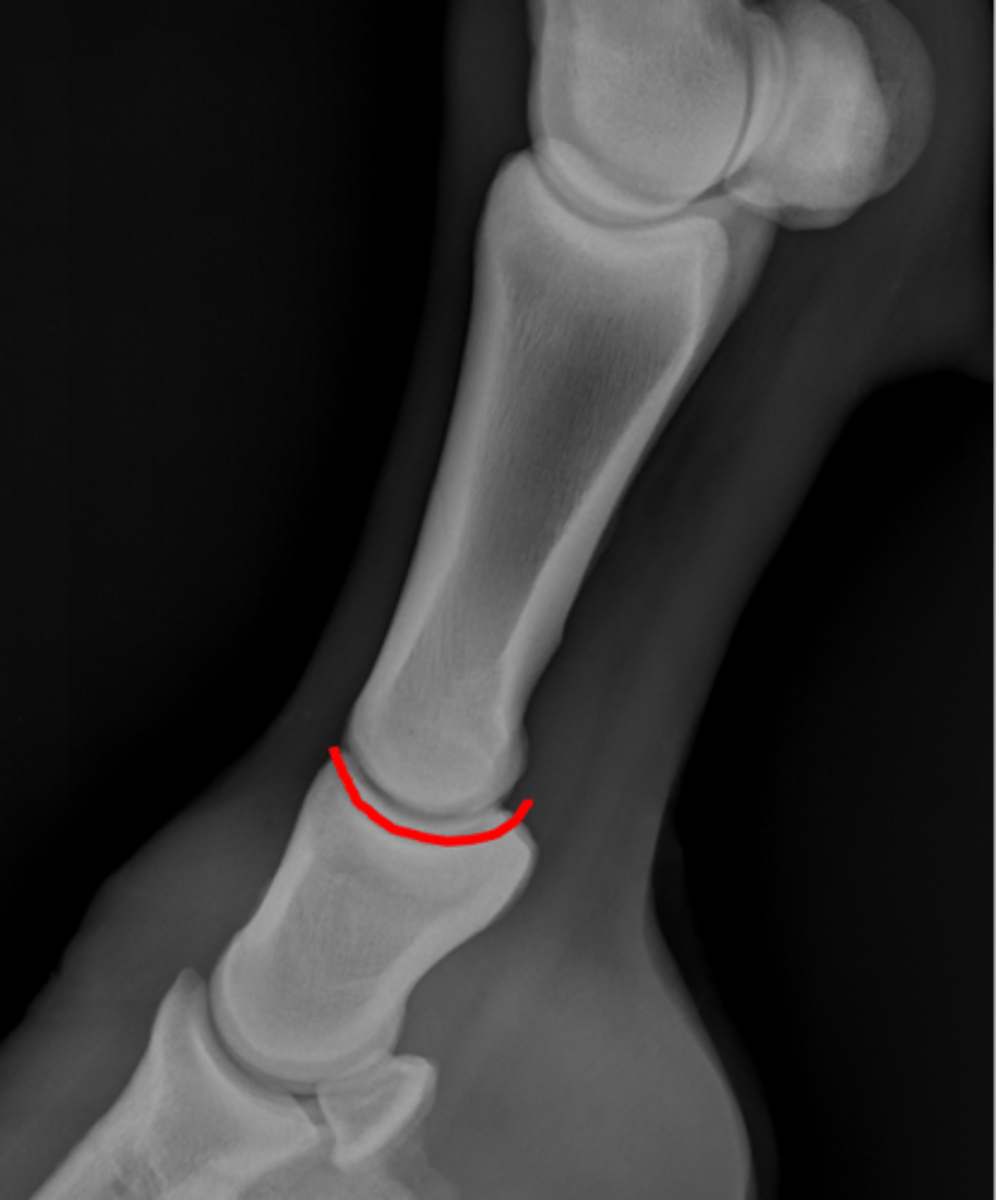

Short pastern (P2)

Long pastern (P1)

Pastern joint (proximal interphalangeal joint)

Long pastern (P1)

Short pastern (P2)

Nutrient foramen of P2

Extensor process of P3

Proximal sesamoid bone

Sagittal ridge

Condyles of third metacarpal bone

Palmar process of P2

Proximal sesamoid bones

Sagittal ridge

Attachment of collateral ligaments

Proximal sesamoid bones

Palmar process of P1

Condyles of the third metacarpal bone